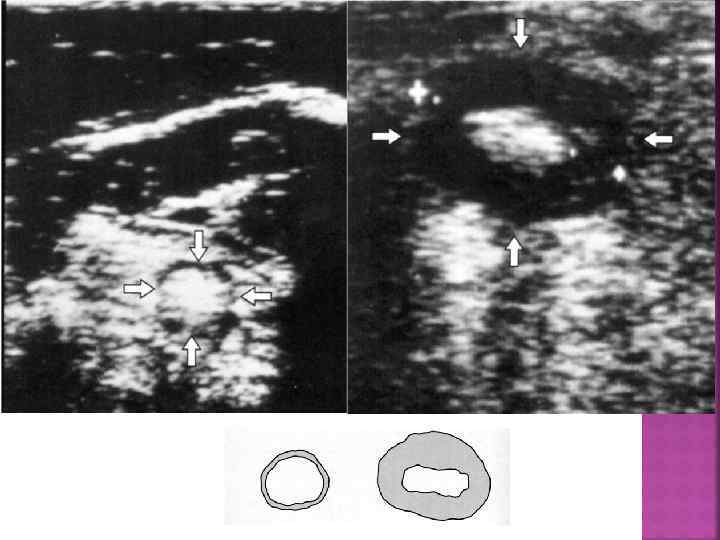

При утолщении кишки вследствие развития в ней какого-либо патологического процесса (отека, кровоизлияния, фиброза, опухоли и т. п. ) нормальные пропорции нарушаются. Периферическое гипоэхогенное кольцо (соответствует стенке кишки) расширяется на том или ином протяжении, а центральная эхогенная часть (соответствует содержимому кишки и складкам слизистой) становится относительно небольшой.

КИ-коэффицент изображения. Опреденяется как отношение максимальной толщины стенки к просвету между стенками.

Неправильная ассиметричная форма Анэхогенная неравномерная периферическая часть (средние значения стенки – 12, 5± 0, 8 мм. ) Узкий, неправильной формы, фрагментированный центр Выраженные диспропорции пораженного участка

Болезнь Крона. Поперечное сечение в правой подвздошной области. Симптом ППО, указывающий на утолщение стенок и сужение полости в области терминального отдела подвздошной кишки.

Утолщение стенки дистального отдела подвздошной кишки при болезни Крона, поперечное изображение.